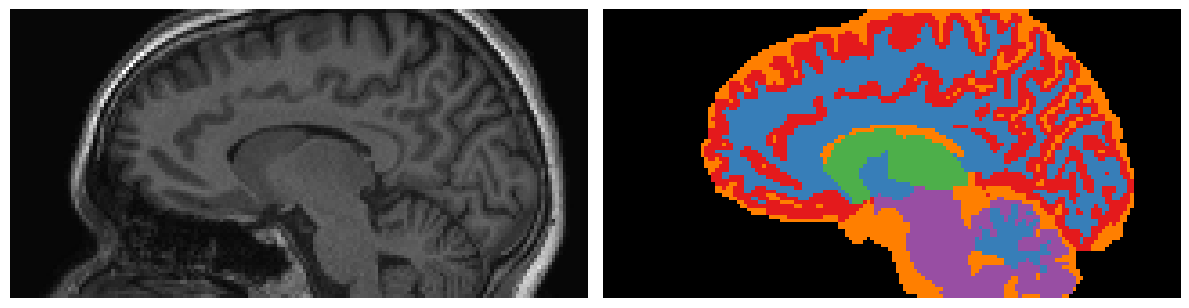

T1-weighted MRI acquired alongside MRE provides high-resolution anatomical structure information. We incorporate these priors into oNLI using whole-brain segmentations generated by SynthSeg billot2023synthseg , which is substantially faster than recon-all from FreeSurfer fischl2012freesurfer while maintaining acceptable accuracy. Segmentations from SynthSeg include over 33 anatomical regions. We group these into six broader categories: cortical gray matter, white matter, and subcortical gray matter, which have statistically distinct material properties hiscox2020standard ; as well as cerebrospinal fluid (CSF), brainstem/cerebellum, and background, which are typically noisy in MRE data and thus treated as separate regions. Segmentation masks are represented as a one-hot encoded vector, resulting in a 6-channel binary segmentation mask of shape {0,1}6×H×W×D\{0,1\}^{6\times H\times W\times D}, where HH, WW, and DD denote the spatial dimensions. Figure 3 shows a representative sagittal slice of a T1-weighted scan and the corresponding anatomical segmentation mask.

Refer to caption

Figure 3: T1-weighted MRI (left) and corresponding 6-region segmentation mask (right) generated using SynthSeg. Regions include: background (black), cortical gray matter (red), white matter (blue), subcortical gray matter (green), brainstem/cerebellum (purple), and cerebrospinal fluid (CSF; orange).